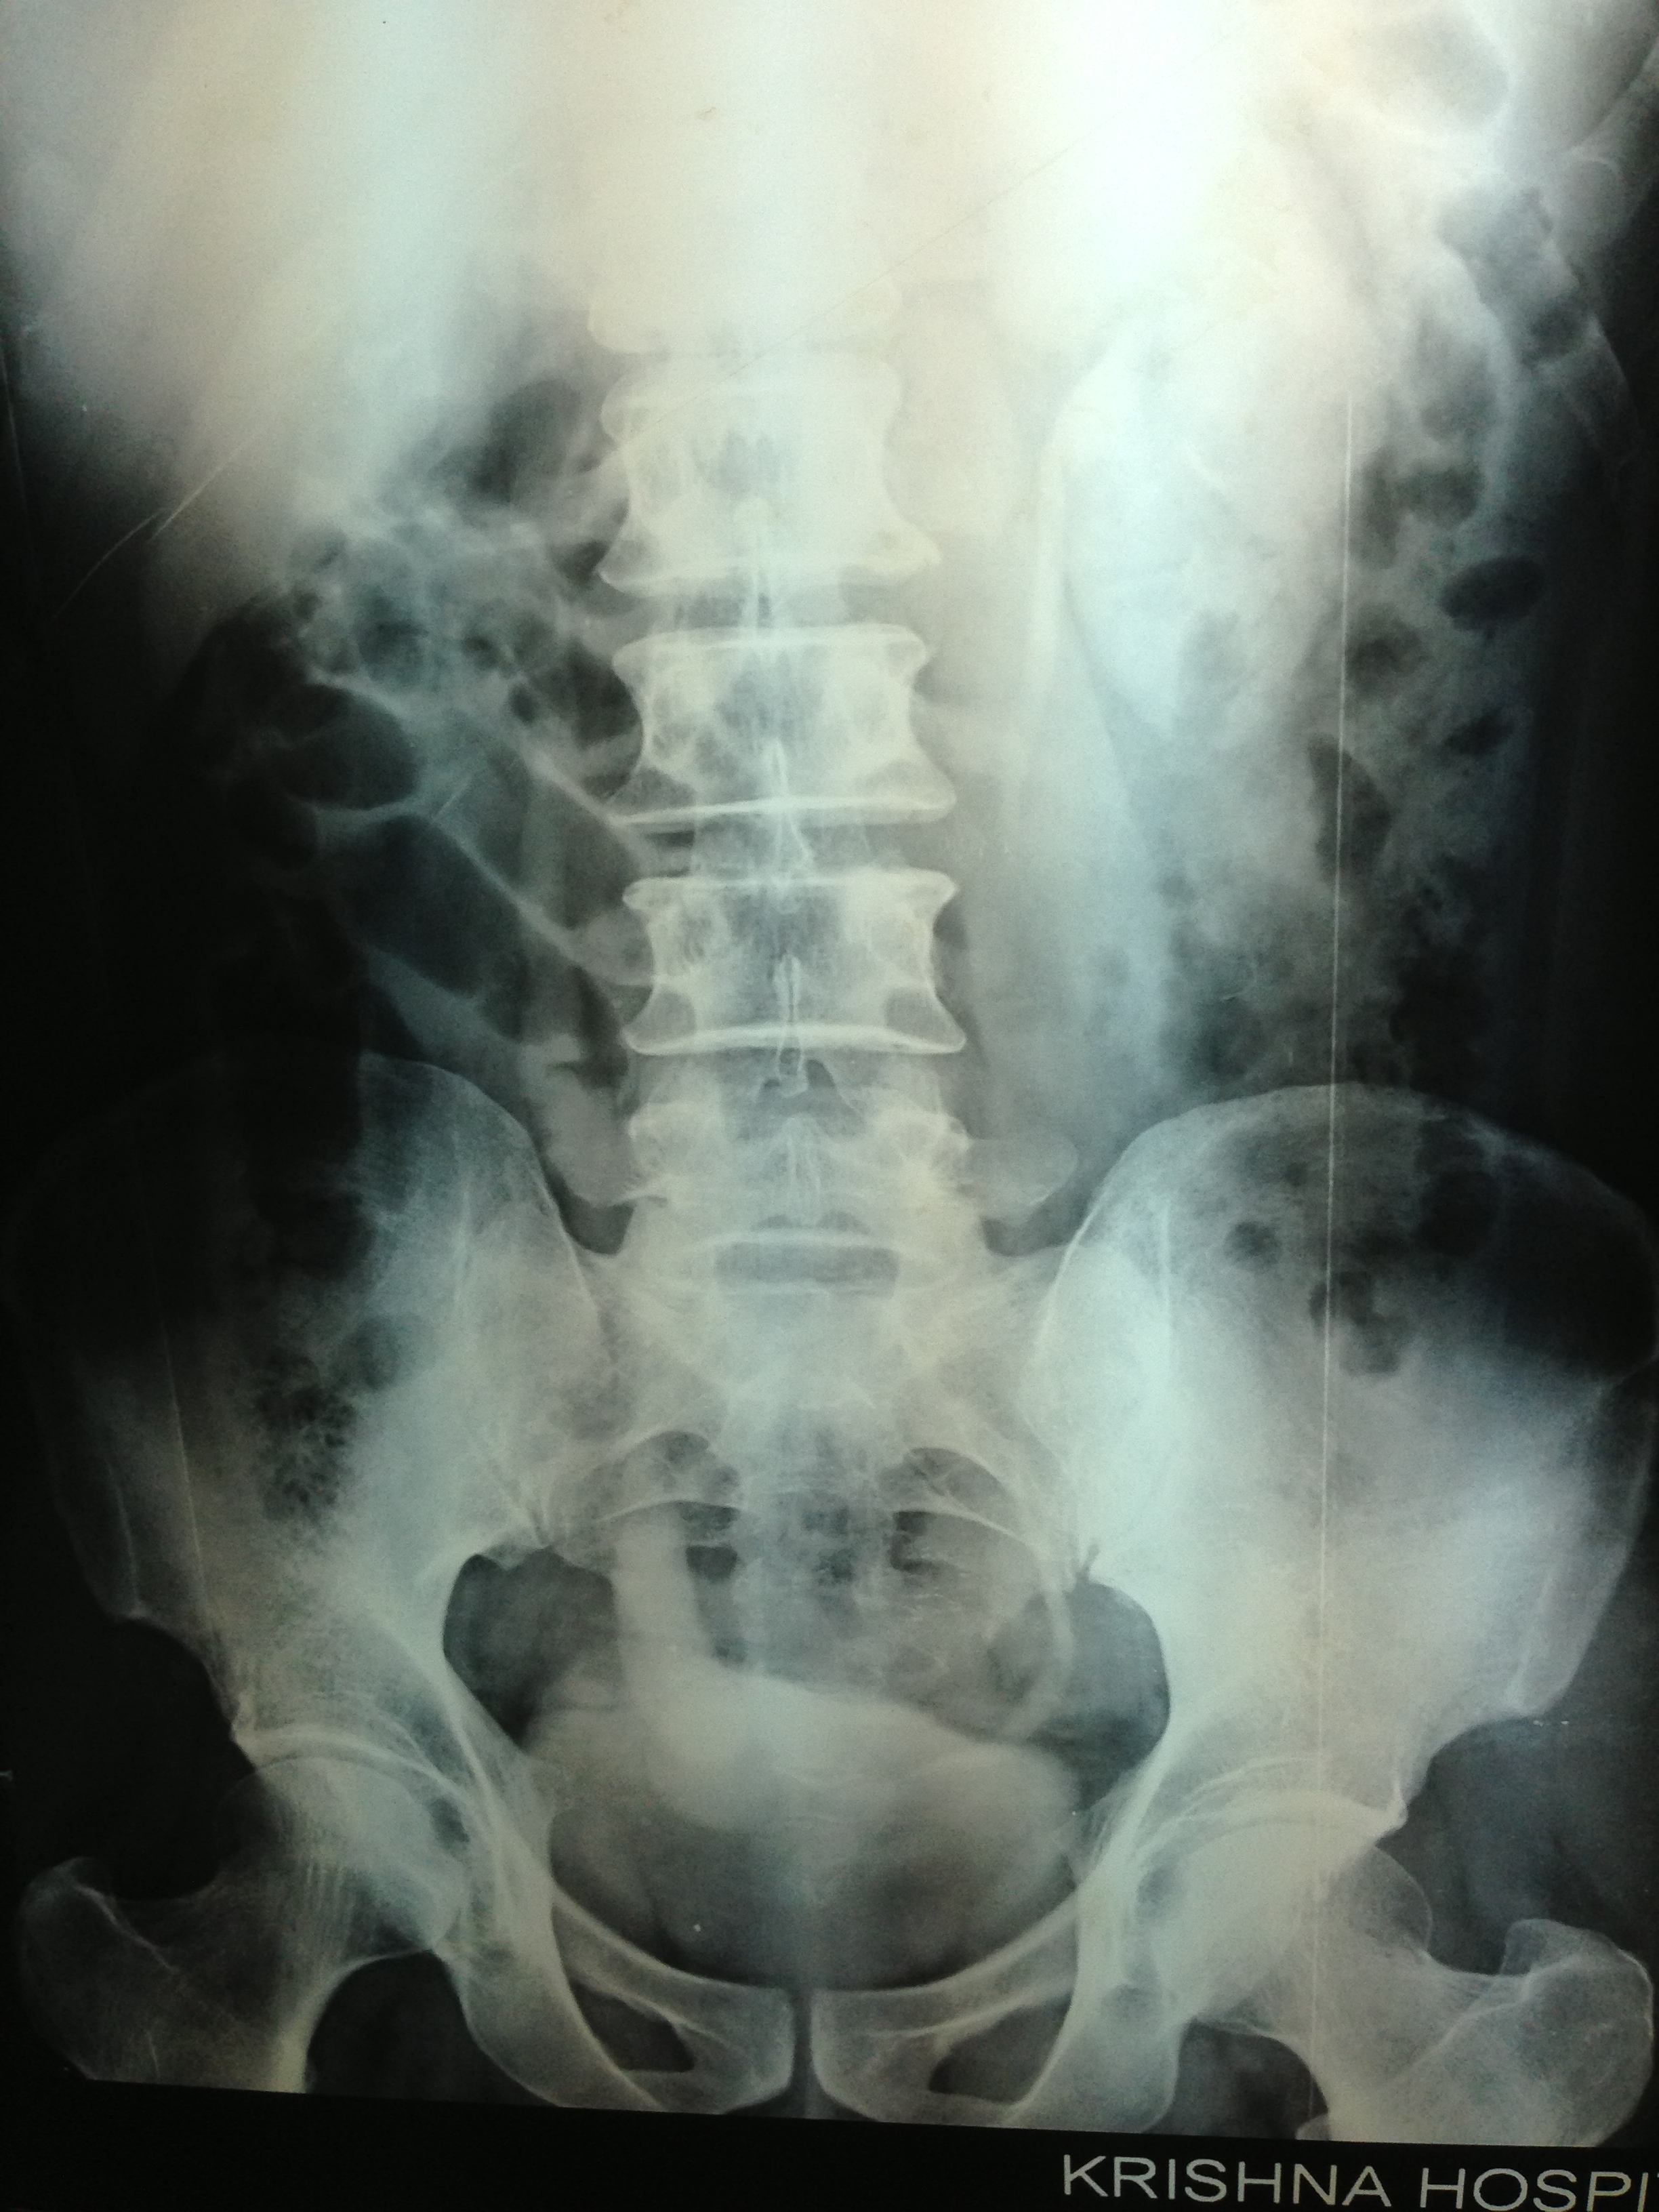

The patient was seen by the urologist and an IVP was done , which proved the diagnosis of orthotopic ureterocele . (a ureterocele entirely within the bladder.)